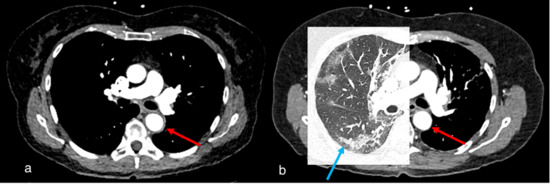

Figure 4.

Case 1, a 67-year-old female. (a) Initial chest CT to clarify pulmonary embolism or post-COVID-19 findings showed concentric wall thickening of the thoracic aorta (red arrow), indicating large vessel vasculitis. No pulmonary infiltrates or post-COVID-19 findings were observed. (b) Follow-up computed tomography 2 months later showed indeterminate appearance of recurrent COVID-19 pneumonia (blue arrow) and regressed arterial wall thickening (red arrow).